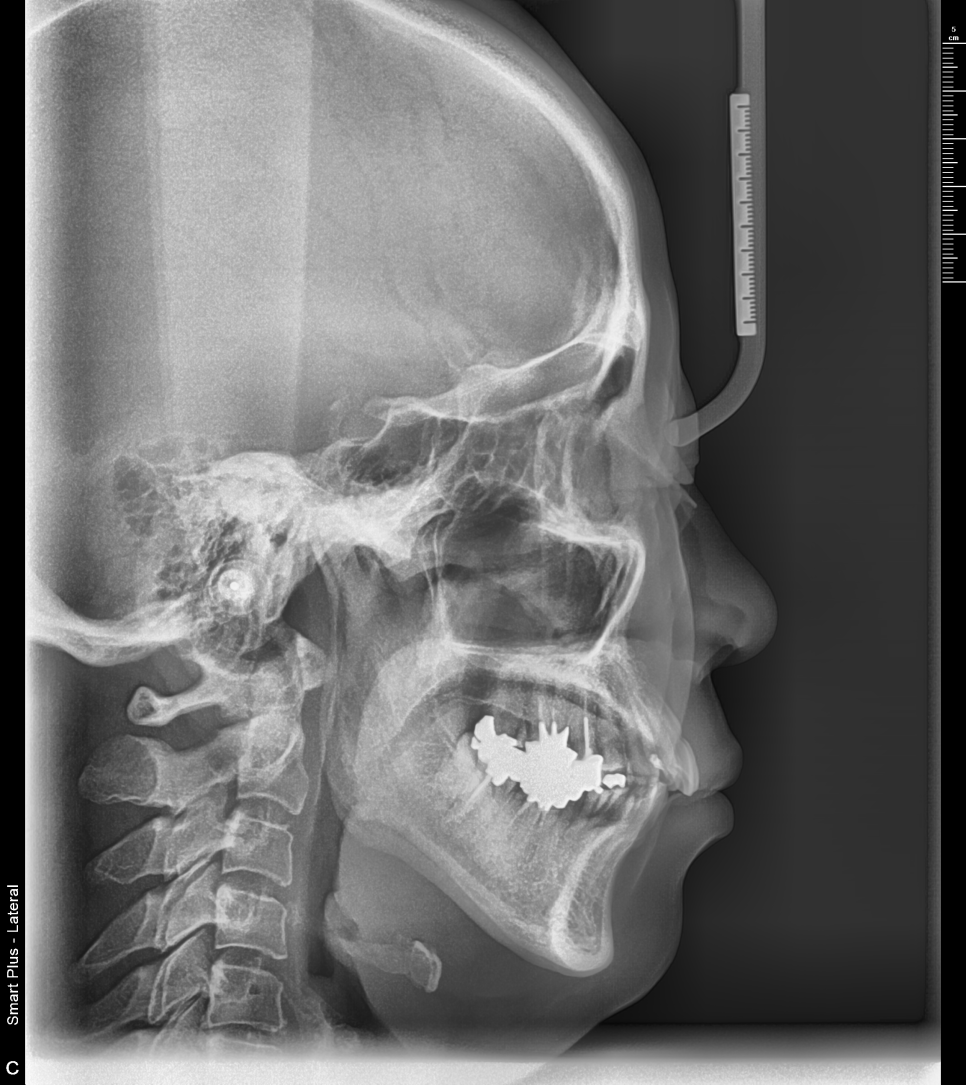

60대 중년여성 진단사진

이분 케이스는 앞니만 부분적으로 교정하시는 것은 한계가 있어서 지금 전체교정을 진행중에 있으십니다.